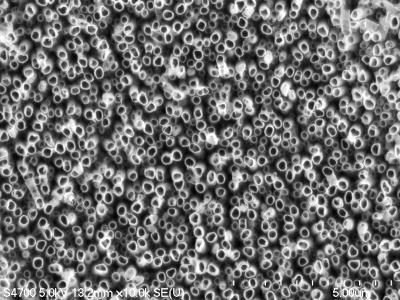

Enter a nano-material that can battle infection, improve healing, and help dental implants last a lifetime: titanium dioxide nanotubes.

Shokuhfar is now working with Cortino Sukotjo, a clinical assistant professor at the University of Illinois at Chicago (UIC) College of Dentistry on a dental implant with a surface made from TiO2 nanotubes, but she has been making and testing them for several years. "We have done toxicity tests on the nanotubes, and not only did they not kill cells, they encouraged growth," she said. She has already demonstrated that bone cells grow more vigorously and adhere better to titanium coated with TiO2 nanotubes than to conventional titanium surfaces. That could keep more dental implants in place.

The TiO2 nanotubes also have a cosmetic advantage: transparency. That's a plus for any dental implant, but especially for a new type made from zirconia, which some patients choose because it is totally white.